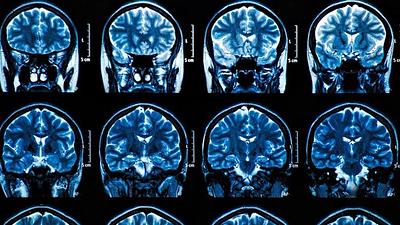

Agência dos EUA aprova medicamento contra Alzheimer

Agências reguladoras de medicamentos dos Estados Unidos (EUA) aprovaram o aducanumab, da Biogen Inc, como primeiro tratamento a combater uma causa provável da doença de Alzheimer, apesar de uma polêmica que questiona se os indícios clínicos provam que o remédio funciona.